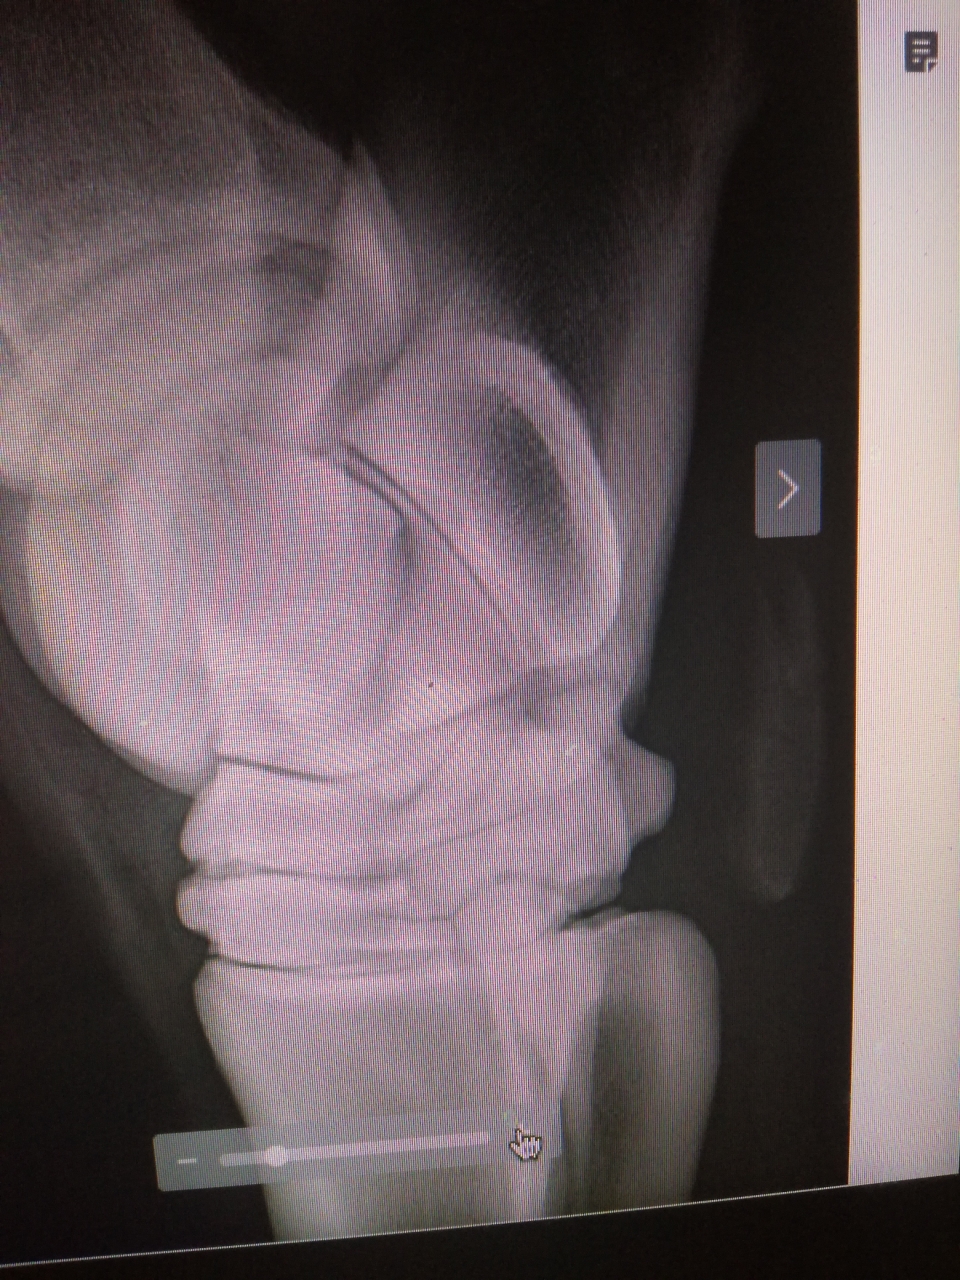

| Dire merci | peuton voir ces fameuses RX ? |

Par sarah69 : le 03/08/19 à 22:10:53

DéconnectéDire merci | v![]() ![]() |

Par sarah69 : le 03/08/19 à 22:11:46

DéconnectéDire merci | desolee por les images mais je ne voulais pas poster en ligne le nom du cheval |

| Dire merci | Mais ce n’est pas d’un antérieur qu’il boite ce cheval? Après en effet s’il a écrit RAS sur les jarrets à la lecture des clichés (bien que vu la qualité on induit plus qu’autre chose) mais de là a parlé d arthrose non par contre d’autres choses pourquoi pas . Message édité le 03/08/19 à 22:49 |

DéconnectéDire merci | excuse moi lapateuh, je n ai pas compris ce que tu veux dire j ai pris une photo des radios...desolee pour la qualité Message édité le 03/08/19 à 22:50 |

| Dire merci | Faire un DG sur deux clichés (en imaginant que ce soit le même membre) c’est quand même un peu légère surtout vu l’image actuellement mise sur le forum. Surtout sans image comparative de l’autre membre. Et je ne comprends pas l’histoire du jarret avec la boiterie d’un antérieur. |

DéconnectéDire merci | l histoire en bref c est que quand le cheval est arrive, je l ai fait parer et il a montre une forte sensibilité et boiterie d un antérieur qui s est bien estompée au bout de quelque jour, du coup, j ai envoye les rx a un veto avec lequel je travail qui m a indique la présence d arthrose au niveau du jarret droit. Le veto de la visite d achat (qui est a 800 km) me dit que non...les radios sont les deux du meme jarret |